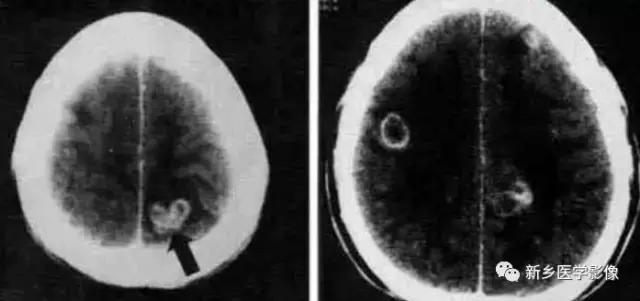

一、TORCH综合症:

TORCH综合症是病毒或原虫感染脑组织引起脑炎。包括弓形体原虫、风疹病毒、巨细胞病毒、疱疹病毒,以疱疹病毒最为常见。主要发生于胚胎期或分娩过程中,故又称先天性宫内感染或先天性TORCH感染。

巨细胞病毒感染引起的钙化常位于脑室周围,可引起胎儿脑发育畸形,如巨脑回畸形、多小脑回畸形、无脑回畸形。

弓形体原虫感染引起的钙化常靠外围,可散在分布于脑实质,往往引起中脑导水管狭窄。

疱疹病毒感染出现钙化可很晚,于3岁后才出现。